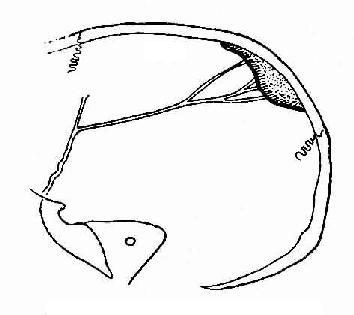

儿童颅内高压所致颅缝分离

图2-23 儿童颅内高压所致颅缝分离

1.冠状缝 2. 人字缝

2.颅缝分离是儿童患者颅内压增加的重要表现。由于儿童的颅缝尚未骨化,所以当颅内压增加时即可分离。